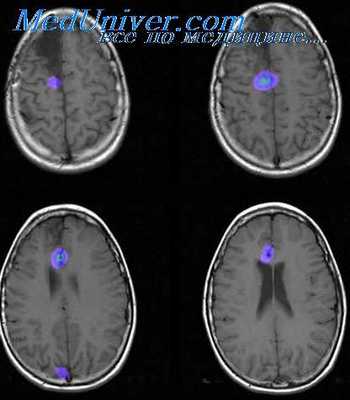

Обследование включало исследование сердца – суточный холтеровский мониторинг ЭКГ и суточный мониторинг артериального давления (СМАД), электроэнцефалографию, с диагностической целью проводились КТ, МРТ исследования. Контрольная группа состояла из 15 практически здоровых лиц от 18 до 36 лет, которым для сравнения проводились холтеровский суточный мониторинг ЭКГ и суточный мониторинг АД.